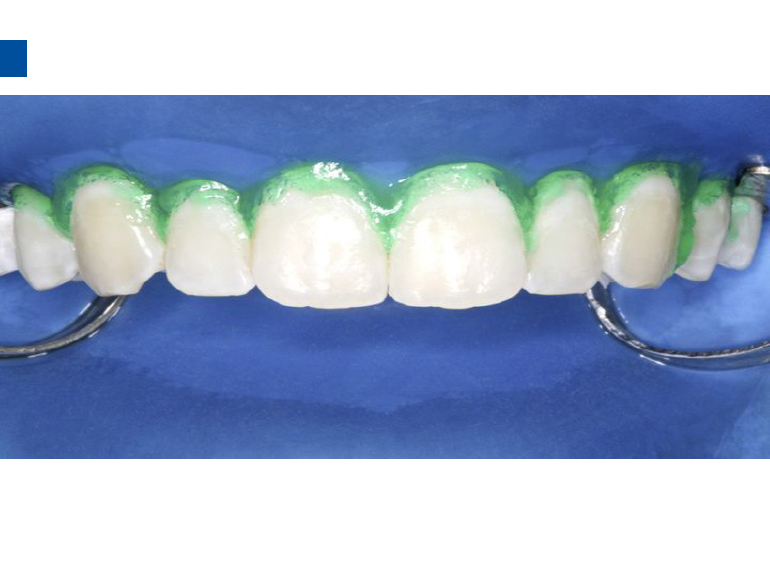

2、将配套唇颊面龋损治疗的注射头装在含有爱康酸蚀剂Icon-Etch的注射器之上。

3、小心旋转注射器柄部,将足量材料涂布于龋损区域之上,等待2分钟,并用棉球去除多余材料,酸蚀范围应至龋损外2mm处,如果正畸患者托槽取下后发现牙面大范围早期龋损则需酸蚀整个牙面。(单手可完成注射器操作)。

4、冲洗爱康酸蚀剂Icon-Etch30秒,吹干

5、将配套注射头装在含爱康干燥剂Icon-Dry的注射器之上,将一半的材料涂布于龋损区,等待30s,吹干